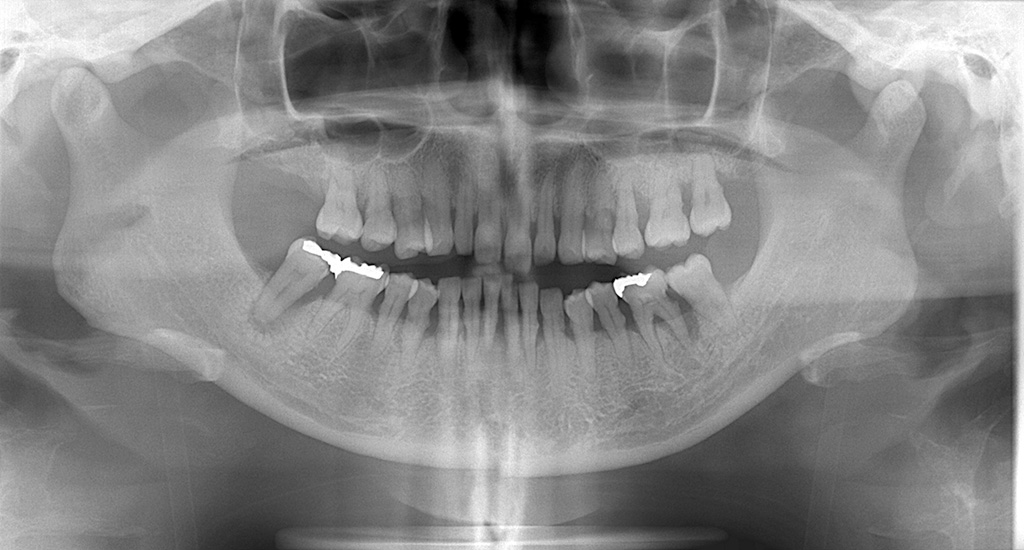

まず見てほしいのがパノラマやデンタルです。

補綴が多いのか?骨吸収があり歯間空隙があるのかを確認します。

歯間空隙が大きい場合は、フロスより歯間ブラシを選択します。

このようなケースでは、

歯間ブラシのほうが 挿入しやすく、

清掃効率も高い ことが多いです。

無理にフロスをすすめるより、

患者さんのストレスを減らし、

習慣化につながります。